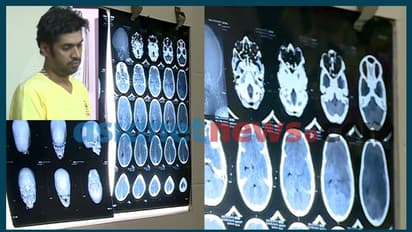

തൊടുപുഴ: തൊടുപുഴയിൽ അമ്മയുടെ സുഹൃത്ത് ക്രൂരമായി മർദ്ദിച്ച ഏഴ് വയസ്സുകാരൻ ജീവനുവേണ്ടി പോരാടുന്നു. വെന്റിലേറ്ററില് മരുന്നുകളുടെ സഹായത്തോടെയാണ് ജീവൻ നിർത്തുന്നത്. പുരോഗതി ഉണ്ടാകാനുള്ള സാധ്യത ഇല്ലെന്നാണ് ഡോക്ടര്മാര് വിലയിരുത്തുന്നത്. കുട്ടിയ്ക്ക് മസ്തിഷ്ക മരണം സംഭവിച്ചതായാണ് നിരീക്ഷണം. ആന്തരിക രക്തസ്രാവം നിയന്ത്രിക്കാനാകാത്തതാണ് ഡോക്ടർമാർ നേരിട്ട പ്രതിസന്ധി.

ക്രൂര മർദ്ദനത്തിൽ കുട്ടിയുടെ തലയോട്ടി പൊട്ടി തലച്ചോറ് പുറത്ത് വന്നിരുന്നു. കുട്ടിയുടെ തലയ്ക്ക് ശസ്ത്രക്രിയ നടത്തിയെങ്കിലും ആരോഗ്യനിലയിൽ ആശാവഹമായ പുരോഗതിയുണ്ടായില്ല. മൂന്നരവയസ്സുള്ള ഇളയകുട്ടി സോഫയിൽ മൂത്രമൊഴിച്ചത് ഏഴ് വയസ്സുകാരന്റെ അശ്രദ്ധയാണെന്ന് ആരോപിച്ചായിരുന്നു മർദ്ദനം. കാലുവാരി ഭിത്തിയിലിടിച്ചതോടെ തലയോട്ടി തകർന്ന് രക്തമൊഴുകി. സോഫയിൽ നിന്ന് വീണ് പരിക്കേറ്റെന്ന് പറഞ്ഞാണ് കുട്ടിയെ ആദ്യം തൊടുപുഴയിലെ ആശുപത്രിയിൽ എത്തിച്ചത്.

പരിശോധനയിൽ തലയോട്ടി പൊട്ടിയെന്ന് വ്യക്തമായതോടെ വിദഗ്ധ ചികിത്സയ്ക്കായി കോലഞ്ചേരി മെഡിക്കൽ കോളേജിലേക്ക് മാറ്റുകയായിരുന്നു. ബുധനാഴ്ച അർദ്ധരാത്രിയാണ് പ്രതി അരുൺ ഉറങ്ങിക്കിടക്കുകയായിരുന്ന ഏഴ് വയസ്സുകാരനെ ക്രൂരമായി മര്ദ്ദിച്ചത്. അരുൺ കുട്ടിയെ നിരവധി തവണ നിലത്തിട്ട് ചവിട്ടുകയും ഭിത്തിയിലിടിക്കുകയും ചെയ്തെന്ന് അമ്മ പൊലീസിന് മൊഴി നൽകിയിട്ടുണ്ട്. സഹോദരനെ വടികൊണ്ട് അടിക്കുന്നത് കണ്ടെന്ന് മൂന്നരവയസുള്ള ഇളയകുട്ടി ചൈൽഡ് വെൽഫെയർ കമ്മിറ്റി അധികൃതരോട് പറഞ്ഞു.